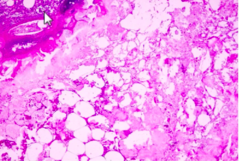

Fat necrosis

Back

-release of pancreatic lipases which cause local destruction of adipocytes -caused by alcoholism, trauma, ischemia, and viral infections -hemorrhagic central areas of liquefaction (firm, gray-white nodules, small chalky white foci with dark hemorrhagic debris -fibrosis-surrounded by fibroblasts -giant cell formation and calcifications -replaced by scar tissue or walled off by fibrous tissue